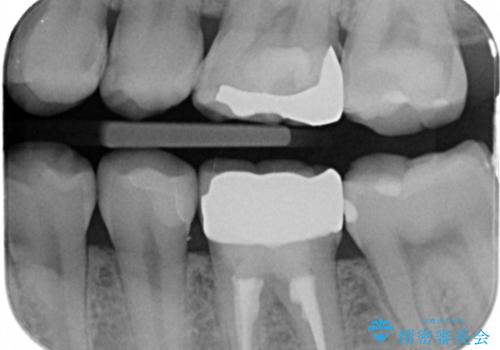

奥の歯と歯の間に虫歯ができていました。

また、歯の外側に古いプラスチックの樹脂で治療されていて劣化していました。

なので詰め物のやりかえだけだと外側を覆うことはできないため被せ物で治療しました。

隣の歯も外側に古いプラスチック樹脂があり、詰め物だと覆えないため被せ物で治療を行いました。